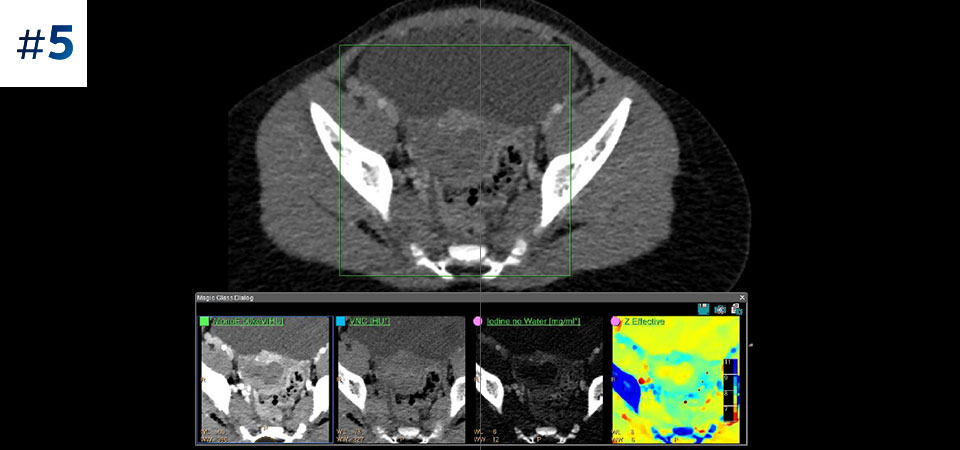

Reduced follow-up exams Improved tissue characterization and visualization may reduce the need for follow-up scanning for sub-optimal exams and incidental findings.

See the difference between spectral-detector CT and conventional CT

Learn about the advantages of spectral-detector CT